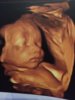

Nydelige gutten vår! ❤️ 29+1